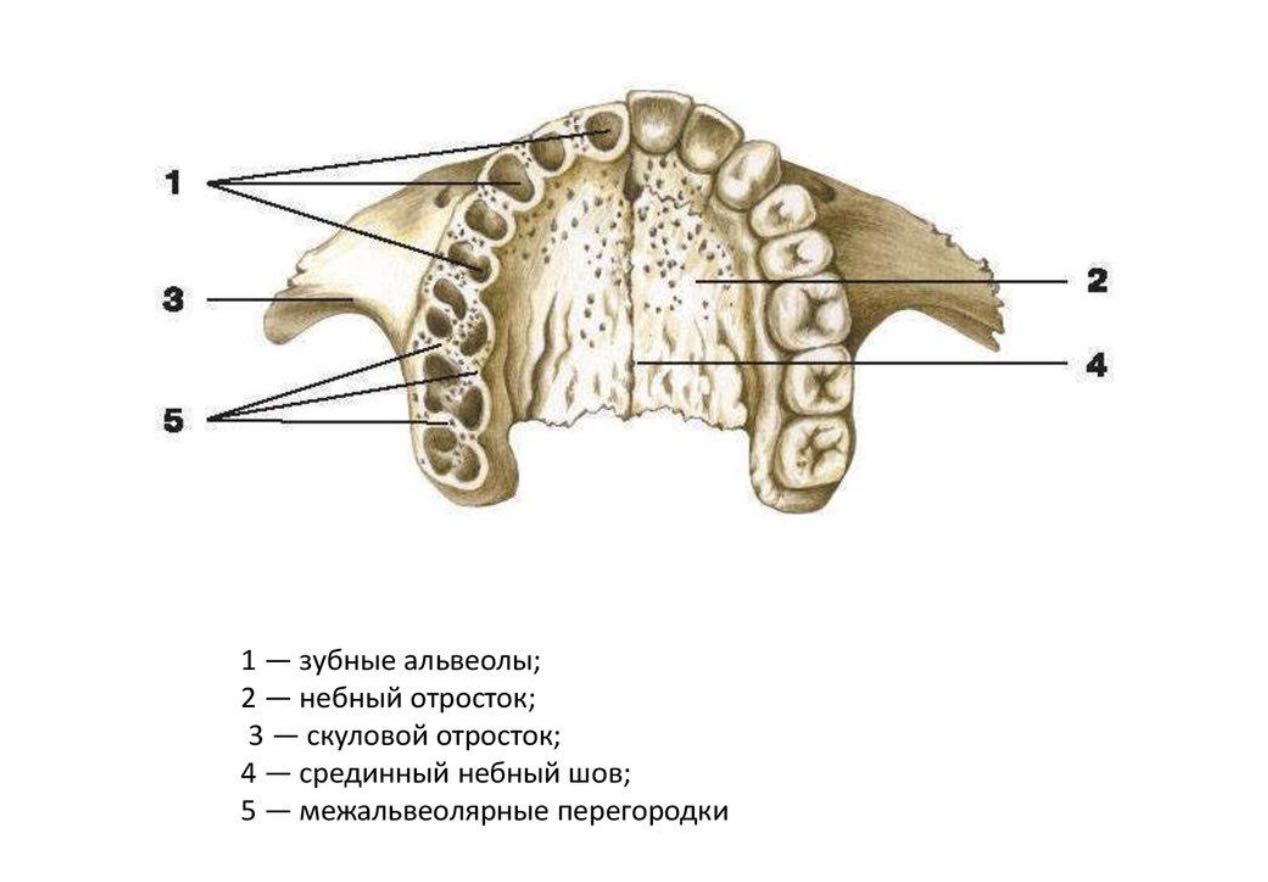

Лечение при помощи брекет-системы позволяет врачу использовать возможности не только дуги, но также микроимплантов. Их можно устанавливать и независимо от брекетов, например, на этапе подготовки для расширения верхней челюсти.